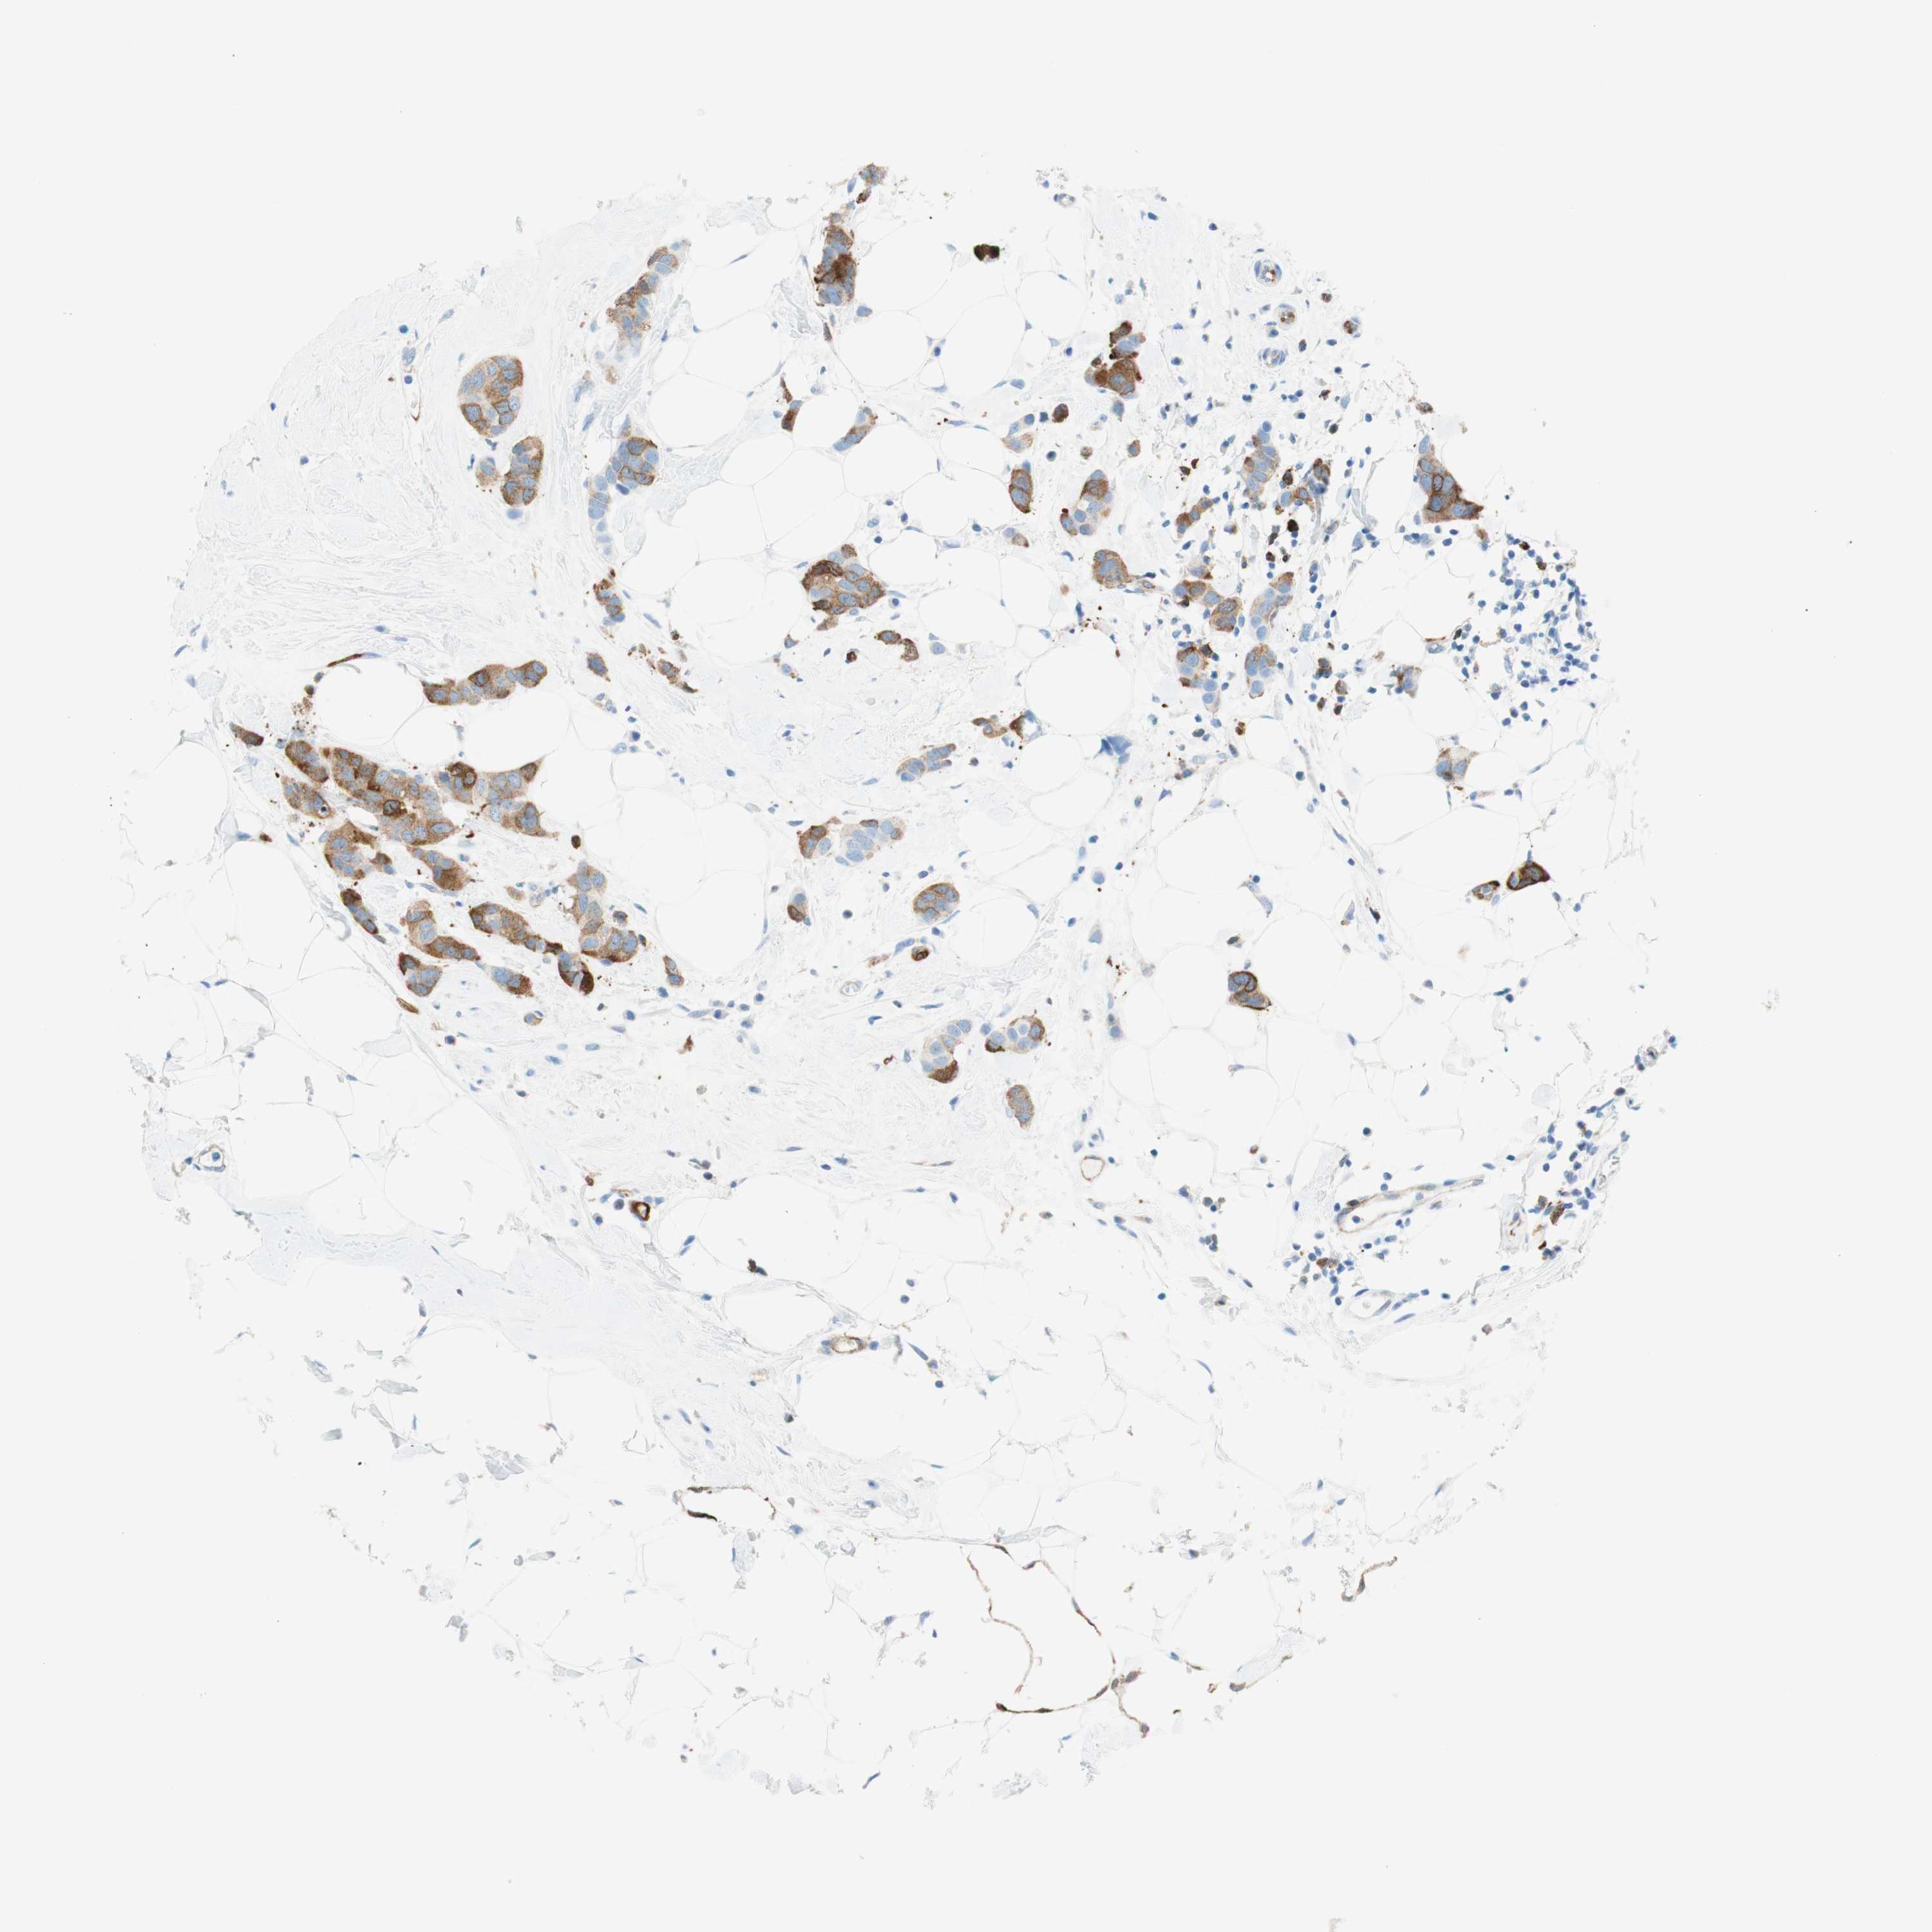

STMN1

CANCER BREAST CANCER Show tissue menu

BRCA TCGA BRCA VALIDATION PROTEIN EXPRESSION

ANTIBODIES

AND

VALIDATION